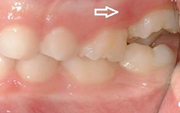

Esimese jäävmolaari ektoopiline lõikumine